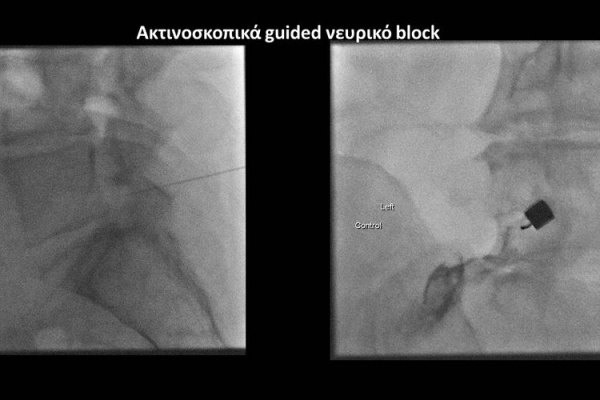

Με την βοήθεια της επεμβατικής ακτινολογίας είναι δυνατόν να πραγματοποιηθούν διαφορες ενέσιμες τεχνικές που αποσκοπούν στη μείωση του μυοσκελετικού πόνου, την ενίσχυση της αποτελεσματικότητας της φυσιοθεραπείας και την επιτάχυνση της διαδικασίας επούλωσης. Οι τεχνικές αυτές περιλαμβάνουν την κατευθυνόμενη έγχυση φαρμάκων ή πραγματοποίηση θεραπευτικών χειρισμών ακριβώς στη θέση τηςπαθολογία. Ετσι εξασφαλιζεται η μέγιστη αποτελεσματικότητα ( έως 95% κατά περίπτωση) και ασφάλεια σε σχέση με τυφλούς χειρισμούς χωρίς ακτινολογική καθοδήγηση.